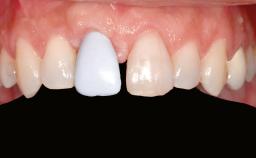

A 46-year-old woman was referred for treatment whose main complaints were mobility of her fixed partial dentures (right maxilla and left mandible) and periodontal bleeding during function. She also reported having taken systemic antibiotics to treat recurrent swelling in the area of the upper left molars. The patient had not seen a dentist for at least 2 years. She did not smoke and had no history of major systemic disease other than two minor orthopedic procedures some years back. The first-visit examination revealed poor plaque control, tooth mobility, periodontal disease, and a residual dentition widely associated with deep periodontal pockets.

Patient's Esthetic Expectations Low Medium High

Lip Line No exposure of papillae Exposure of papillae Full exposure of mucosa margin

Periodontal Phenotype Low-scalloped, thick Medium-scalloped, medium-thick High-scalloped, thin

Shape of Tooth Crowns Rectangular Triangular